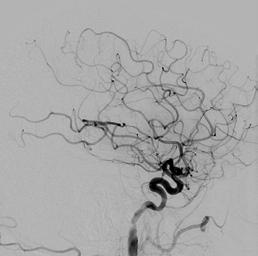

I mages from the embolectomy procedure performed on the patient whose CT perfusion image is on the cover. Both the “before” and “after” are lateral projections with the x-ray camera positioned over the patient’s head.

The “before” image has a paucity of blood vessels because there is a blood clot in the middle cerebral artery that is occluding flow into all of the branches from the middle cerebral artery. The “after” image was obtained after the embolectomy procedure was performed to remove the blood clot in the middle cerebral artery. This shows restoration of normal blood flow to the brain.

Comparing the “before” and “after” images shows the very large number of blood vessels, and subsequent area of the brain, that were at risk of causing permanent stroke for the patient. Thankfully, the blood vessels were able to be reopened in time and the patient made a full recovery.

BEFORE AFTER